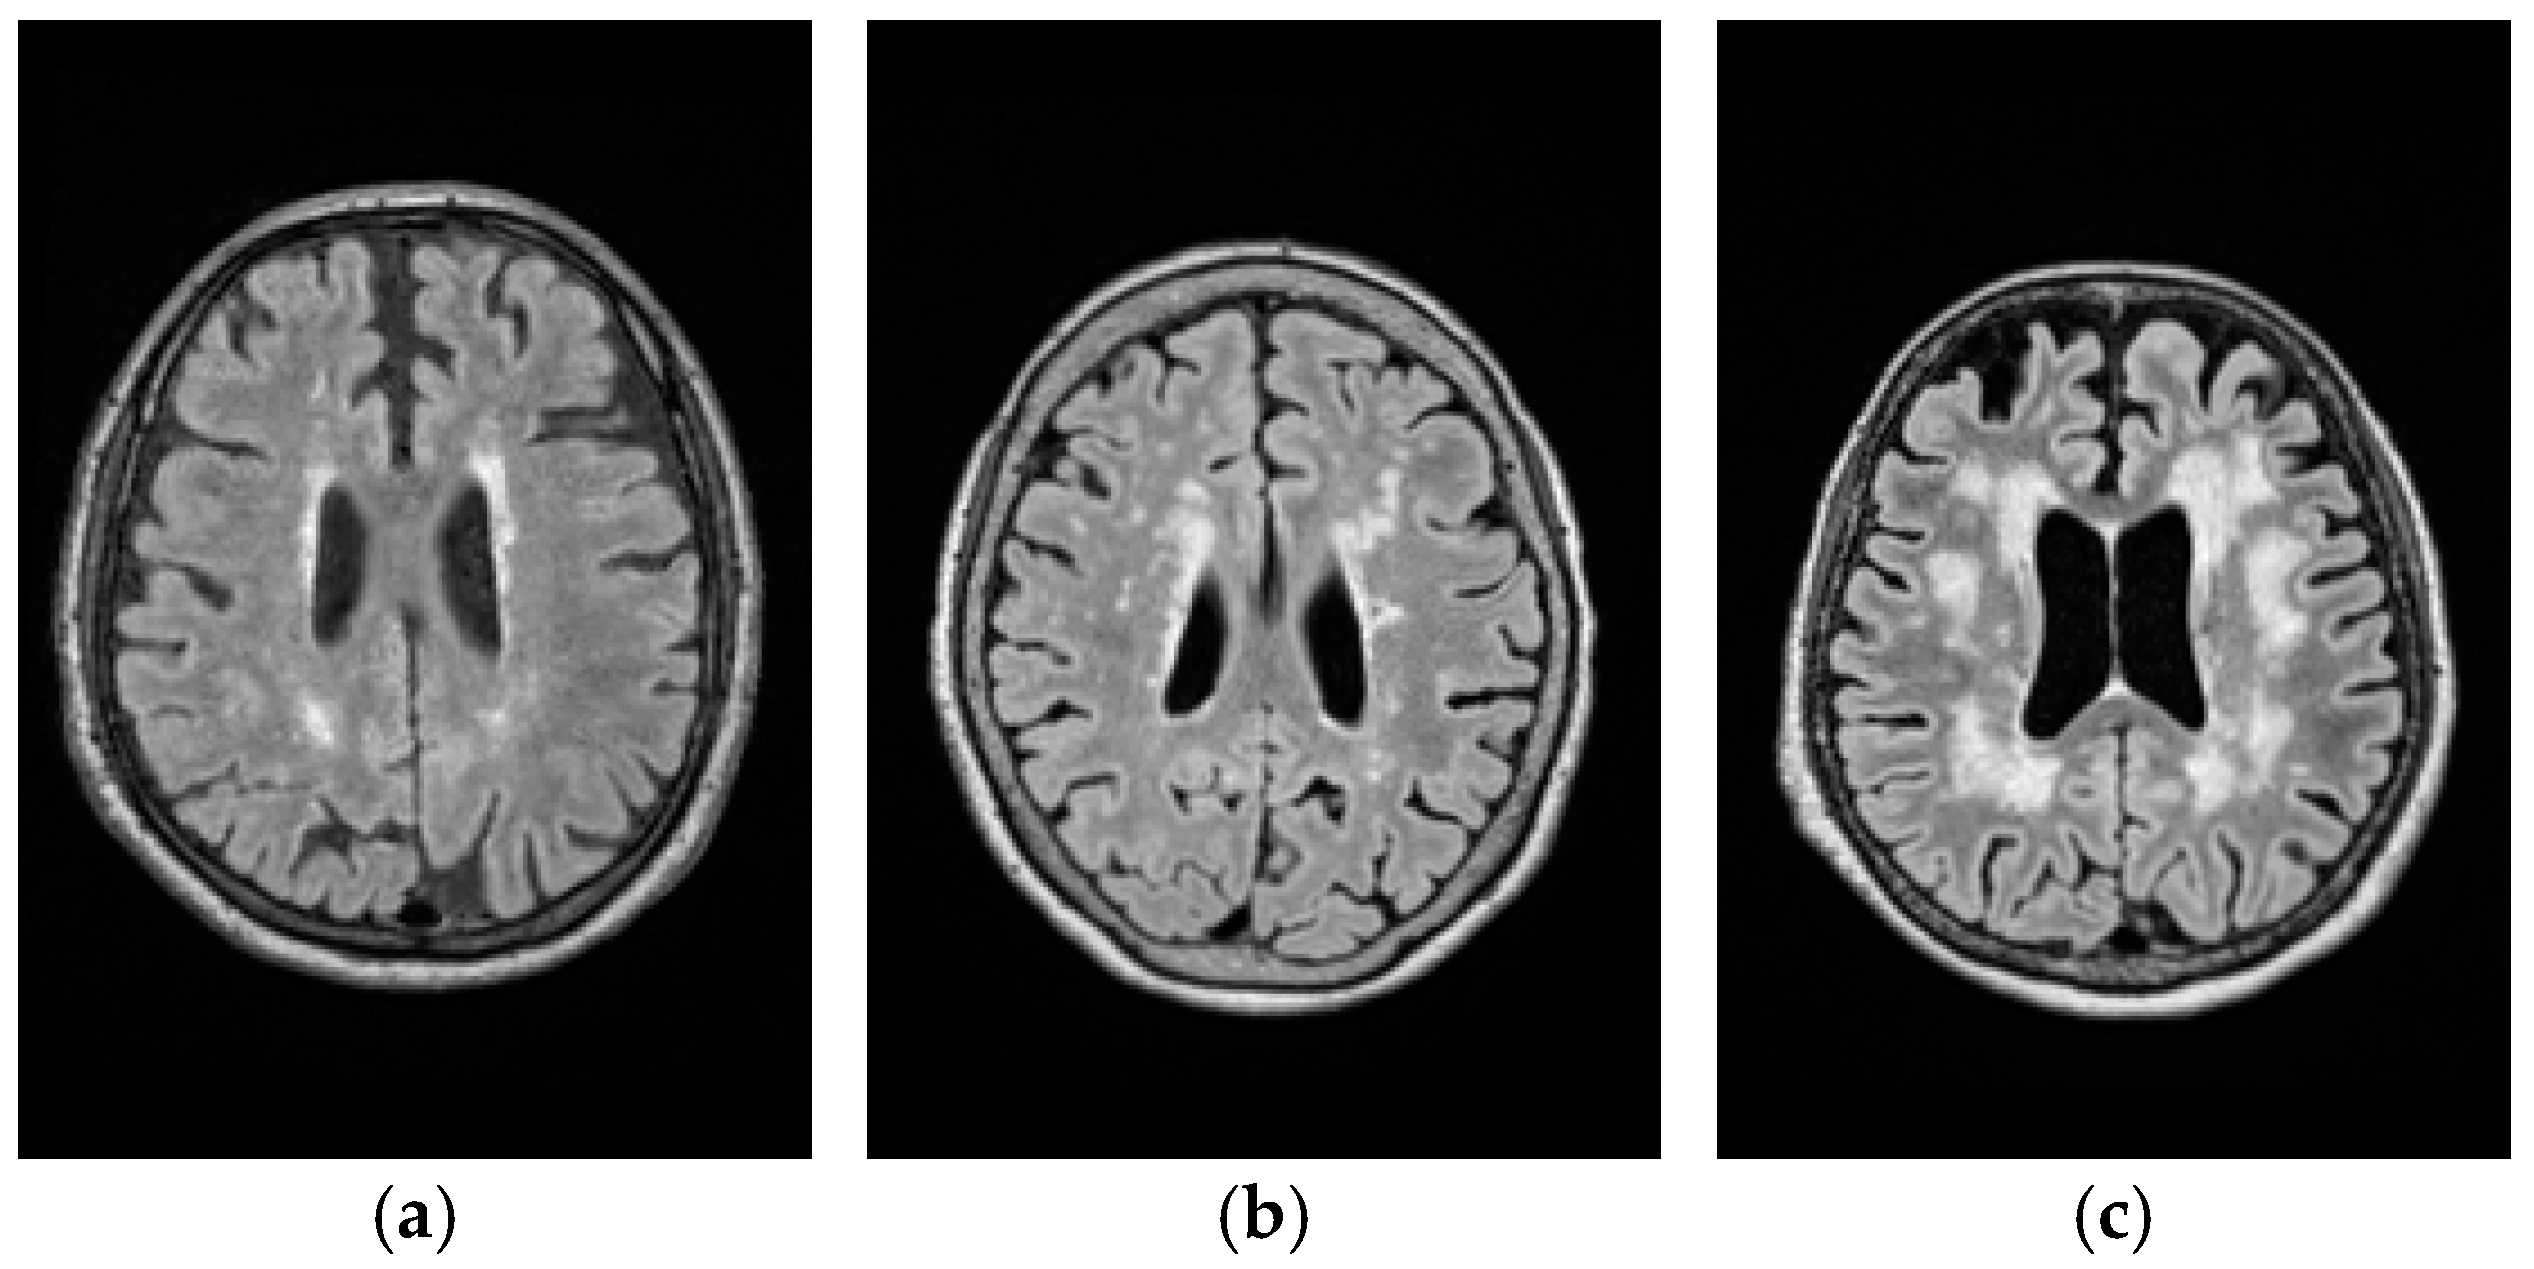

Real MRI brain images were acquired at the Taichung Veterans General Hospital (TCVGH) by Siemens Magnetom Aera 1.5 Tesla (Erlangen, Germany) MR scanner with a 16-channel phase-array head coil. MR imaging protocol included T1W with 3D MPRAGE, T2W and FLAIR. Since T1W, T2W and FLAIR images used for experiments were collected by 3D high resolution sequences with each voxel of size, 1 × 1 × 1 mm3, the interpolation artifacts and partial volume do not have much effect on imaging. However, as a part of trade-off, this also requires additional 2 min for image acquisition. Other imaging parameters used for data acquisition were voxel size of 1 × 1 × 1 mm3, matrix size = 256 × 256 × 176, NEX = 1. According to a clinical visual inspection criterion [27], the WMH lesions can be graded by Fazekas with three grades of Fazekas shown in Figure 11 for illustration.

Figure 11.

Lesion categorized by three grades of Fazekas shown in FLAIR images. (a) Fazekas grade 1; (b) Fazekas grade 2; (c) Fazekas grade 3

A total of 111 cases were collected and all the participants have been well-informed and signed their consents. In addition, the study conducted in this paper was approved by the Ethics Committee of Clinical Research, Taichung Veterans General Hospital (IRB number: CE16138A). Among all the 111 cases there are 58 cases of Fazekas grade 1, 44 cases of Fazekas grade 2 and 9 cases of Fazekas grade 3. Thus, in this study, we selected 10 cases from Fazekas grade 1, 11 cases from Fazekas grade 2, and 9 cases from Fazekas grade 3.

Figure 12, Figure 13 and Figure 14 show the WMH lesion detection results produced by CBEP-ICEM2 and LST for three Fazekas grades, respectively, where Figure 12a, Figure 13a and Figure 14a are original T1W, T2W and FLAIR MR images; Figure 12b, Figure 13b and Figure 14b are iterative WMH lesion detection images by CBEP-ICEM2 along with final WMH lesion detection by Otsu’s method; and Figure 12c, Figure 13c and Figure 14c show comparisons between lesion detections by CBEP-ICEM2 and LST.

Figure 14.

Lesion detection of Fazekas grade 3 By CBEP-ICEM2 and LST. (a) Original MR images (T1W, T2W, FLAIR) with lesions of Fazekas grade 3; (b) Lesion detection by CBEP-ICEM2; (c) Comparison between lesion detections by CBEP-ICEM2 and LST.